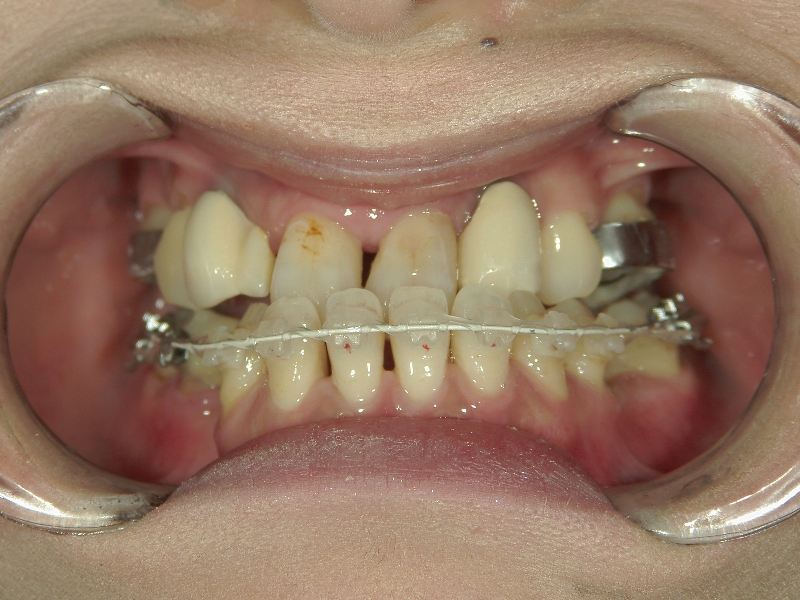

上顎に比べ、下顎が著しく後退しています。

上の歯と下の歯を斜めに繋ぐようにツインフォースという装置を装着します。装置の力で、顎が前方へ押し出されてきました。

顎の移動が終了しました。装置を外して、今後はワイヤーを使用して歯列を治します。

矯正治療後の後戻りを想定して、あえて必要量を越えた顎の移動を行います。